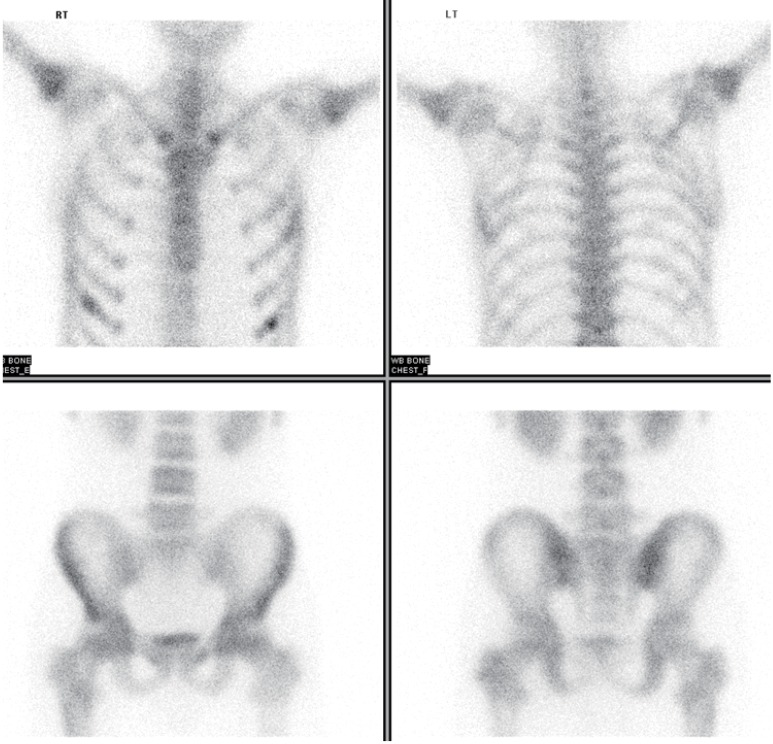

Mildly increased parenchymal echogenicity was observed on a renal ultrasonography. Rradiography of the pelvis showed focal osteolytic lesions in the intertrochanteric area of right femur (Fig. 1). A coronal spin echo T1-weighted magnetic resonance image showed diffuse decreased marrow signal intensity in the vertebral column, pelvic bones, and both femurs, and several focal osteonecrotic areas in both iliac wings and the intertrochanteric area of the right femur (Fig. 2). There was mild and diffusely increased tracer uptake on both proximal humeri and femurs on a whole body bone scan with 99mTc hydroxymethylene diphosphonate (Fig. 3).

Fig. 3. There was mild and diffusely increased tracer uptake on both proximal humeri and femurs on a whole body bone scan with 99mTc hydroxymethylene diphosphonate.